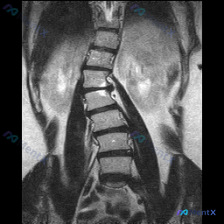

整理到一张腰椎MRI的冠状位T1WI图像,先不说结论,大家第一眼会怎么看? 目前能看到的影像表现: - 腰椎明显向右侧凸,有椎体旋转和倾斜 - 两侧椎间隙高度不均匀,部分变窄 - 多个椎间盘信号降低 - 椎体骨髓信号基本是弥漫中等偏高,没看到明确的局灶骨质破坏或大肿块 - 两侧腰大肌形态不对称 这份...

整理了一份腰椎MRI的影像资料,先放出来大家一起讨论。 核心影像表现(冠状位 T1 加权): 1. 腰椎序列存在轻度向左侧的代偿性弯曲 2. 下腰椎段(L4-L5 及 L5-S1)椎间隙明显狭窄,信号减低 3. 对应椎体边缘可见骨赘增生,伴骨质硬化或不规则改变 4. 小关节可见明显增生肥大,尤其是下...

整理到一份影像读片资料,有点意思,放出来讨论下。 先看核心发现: - 腰椎MRI T2冠状位:明显向左侧凸畸形;椎体边缘骨赘形成,部分椎间隙非对称性变窄;凹侧椎间孔区域相对狭窄。 - 额外发现:右侧(图像左侧)肾脏内见边界尚清的明显高信号影。 影像科初步分析里提了“退行性脊柱侧弯”的依据很足,但同时...

整理到一份胸部冠状位MRI T1加权像的读片资料,先把影像描述放出来,大家来找找核心问题是什么: - 双侧胸壁肌肉信号基本对称,皮下脂肪清晰; - 纵隔气管、主动脉弓走行基本正常,未见纵隔肿块; - 双肺野呈均匀低信号(MRI肺内含气的正常表现); - 各椎体形态基本完整,骨髓信号均匀(T1加权像下...